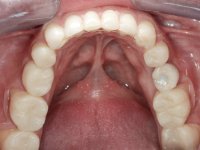

Paciente do sexo masculino, com 36 anos, não fumador. Fez tratamento ortodôntico e reabilitou esteticamente o sector anterior com restaurações em resina composta. As restaurações apresentavam um aumento vertical médio de 2 mm em relação o bordo incisal. Apresentavam-se esteticamente satisfatórias, mas com algumas fraturas incisais. O dente 1.5 apresentava um processo apical e o dente 2.6 apresentava tratamento endodôntico e uma lesão endo-periodontal. No maxilar inferior no local do dente 3.5 apresentava um implante com uma coroa aparafusada e o dente 8.5 ainda estava presente em boca com agenesia do dente 4.5. O paciente apresentava uma ligeira perda da dimensão vertical da oclusão provavelmente associada a um visível desgaste das superfícies oclusais. O periodonto era espesso e apresentava uma excelente higiene oral.

Realizado o diagnóstico e tomada a decisão quanto ao tratamento a executar, tornou-se importante definir qual a sequência de trabalho a adotar no sentido de conseguir a reabilitação da D.V.O. (V.D.O), de forma progressiva e equilibrada. Na primeira fase fez-se uma pré-impressão da arcada inferior com silicone tipo “putty” e em seguida realizou-se o preparo dentário de todo o sector posterior. O preparo para os overlays foi feito coronalmente à linha amelo cementaria no sentido de ser o mais conservador possível. A impressão foi feita com técnica de dupla mistura após afastamento gengival realizado com pasta de caulino. A provisória foi realizada com resina composta de polimerização dual. Em laboratório foram realizados os overlays após se ter aberto ligeiramente (1,5mm) a D.V.O. nos modelos montados em articulador semi-ajustável. Simultaneamente o sector antero-inferior foi encerado no sentido de acompanhar este aumento da D.V.O. Também foi confecionada uma chave de silicone translucido para posterior confeção dos provisórios antero-inferiores. Em boca foi primeiro realizada a provisionalização dos dentes anteriores utilizando resina composta previamente aquecida após preparação das superfícies dentárias para a adesão. Foi colocado o dique de borracha para promover o isolamento absoluto e posteriormente foram colados os overlays. Em laboratório foi realizada nova chave de silicone para confecionar os provisórios antero-superiores. Seguidamente em boca foram preparados os seis dentes antero-superiores após colocação do fio de afastamento gengival. Feita a preparação adequada das superfícies dentárias foi realizada a impressão com técnica de dupla mistura e a respetiva provisória. Em laboratório foram confecionadas 6 facetas feldespáticas num modelo de trabalho tipo “Geller”. A provisória foi removida e as facetas foram coladas em boca utilizando um isolamento relativo competente. Esta opção foi tomada em virtude de uma prévia experiencia negativa com a colocação do dique de borracha na mandibula. Após a colagem dos laminados antero-superiores foram dadas 12 semanas para avaliar a adaptação do paciente à nova situação e então iniciar a confeção das facetas antero-inferiores. Após colocação do fio de afastamento gengival. foram feitos os preparos dentários adequados e em seguida foi feita a impressão. Também foi feita a preparação do dente 3.4 que, entretanto, tinha sofrido uma fratura do overlay. As facetas e a restauração do 3.4 foram realizadas num modelo de trabalho tipo “Geller”. Após remoção da provisória, as facetas foram coladas em boca, utilizando um isolamento relativo pelas razões apontadas anteriormente. Após colocação do trabalho o paciente foi reabilitado por outros colegas com um implante na zona do 2.6 e substituição da coroa aparafusada sobre o implante colocado no local do 3.5. Posteriormente surgiram fraturas nos overlays dos dentes 4.7 e 3.7 que foram reabilitados com overlays em Zr.